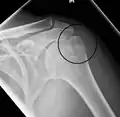

Fracture of the greater tuberosity of the humerus

Multi-fragmented, or comminuted fracture of the proximal humerus with involvement of the greater tuberosity